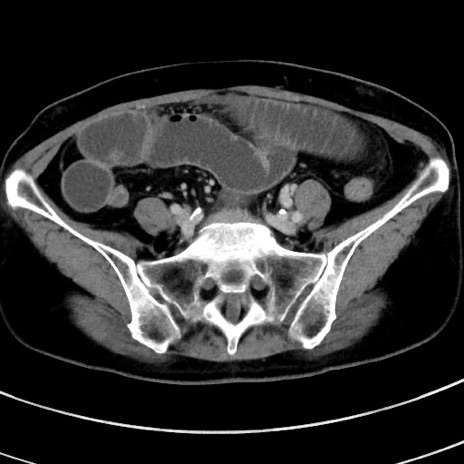

症例9(横断像)

【症例】 60歳代女性

【主訴】むかつき、みぞおちの痛み

【現病歴】3日前よりむかつきがあり、食事がとれない。

【既往歴】糖尿病

【身体所見】発熱なし、心窩部圧痛軽度あるも、腹膜刺激症状なし。

【データ】WBC 7400、CRP 1.92